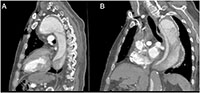

Figure 2: Sagittal slices of the proximal aortic arch aneurysm, and the descending aortic aneurysm with contrast dye enhanced perfusion, and a 90° angulation at the diaphragm level.